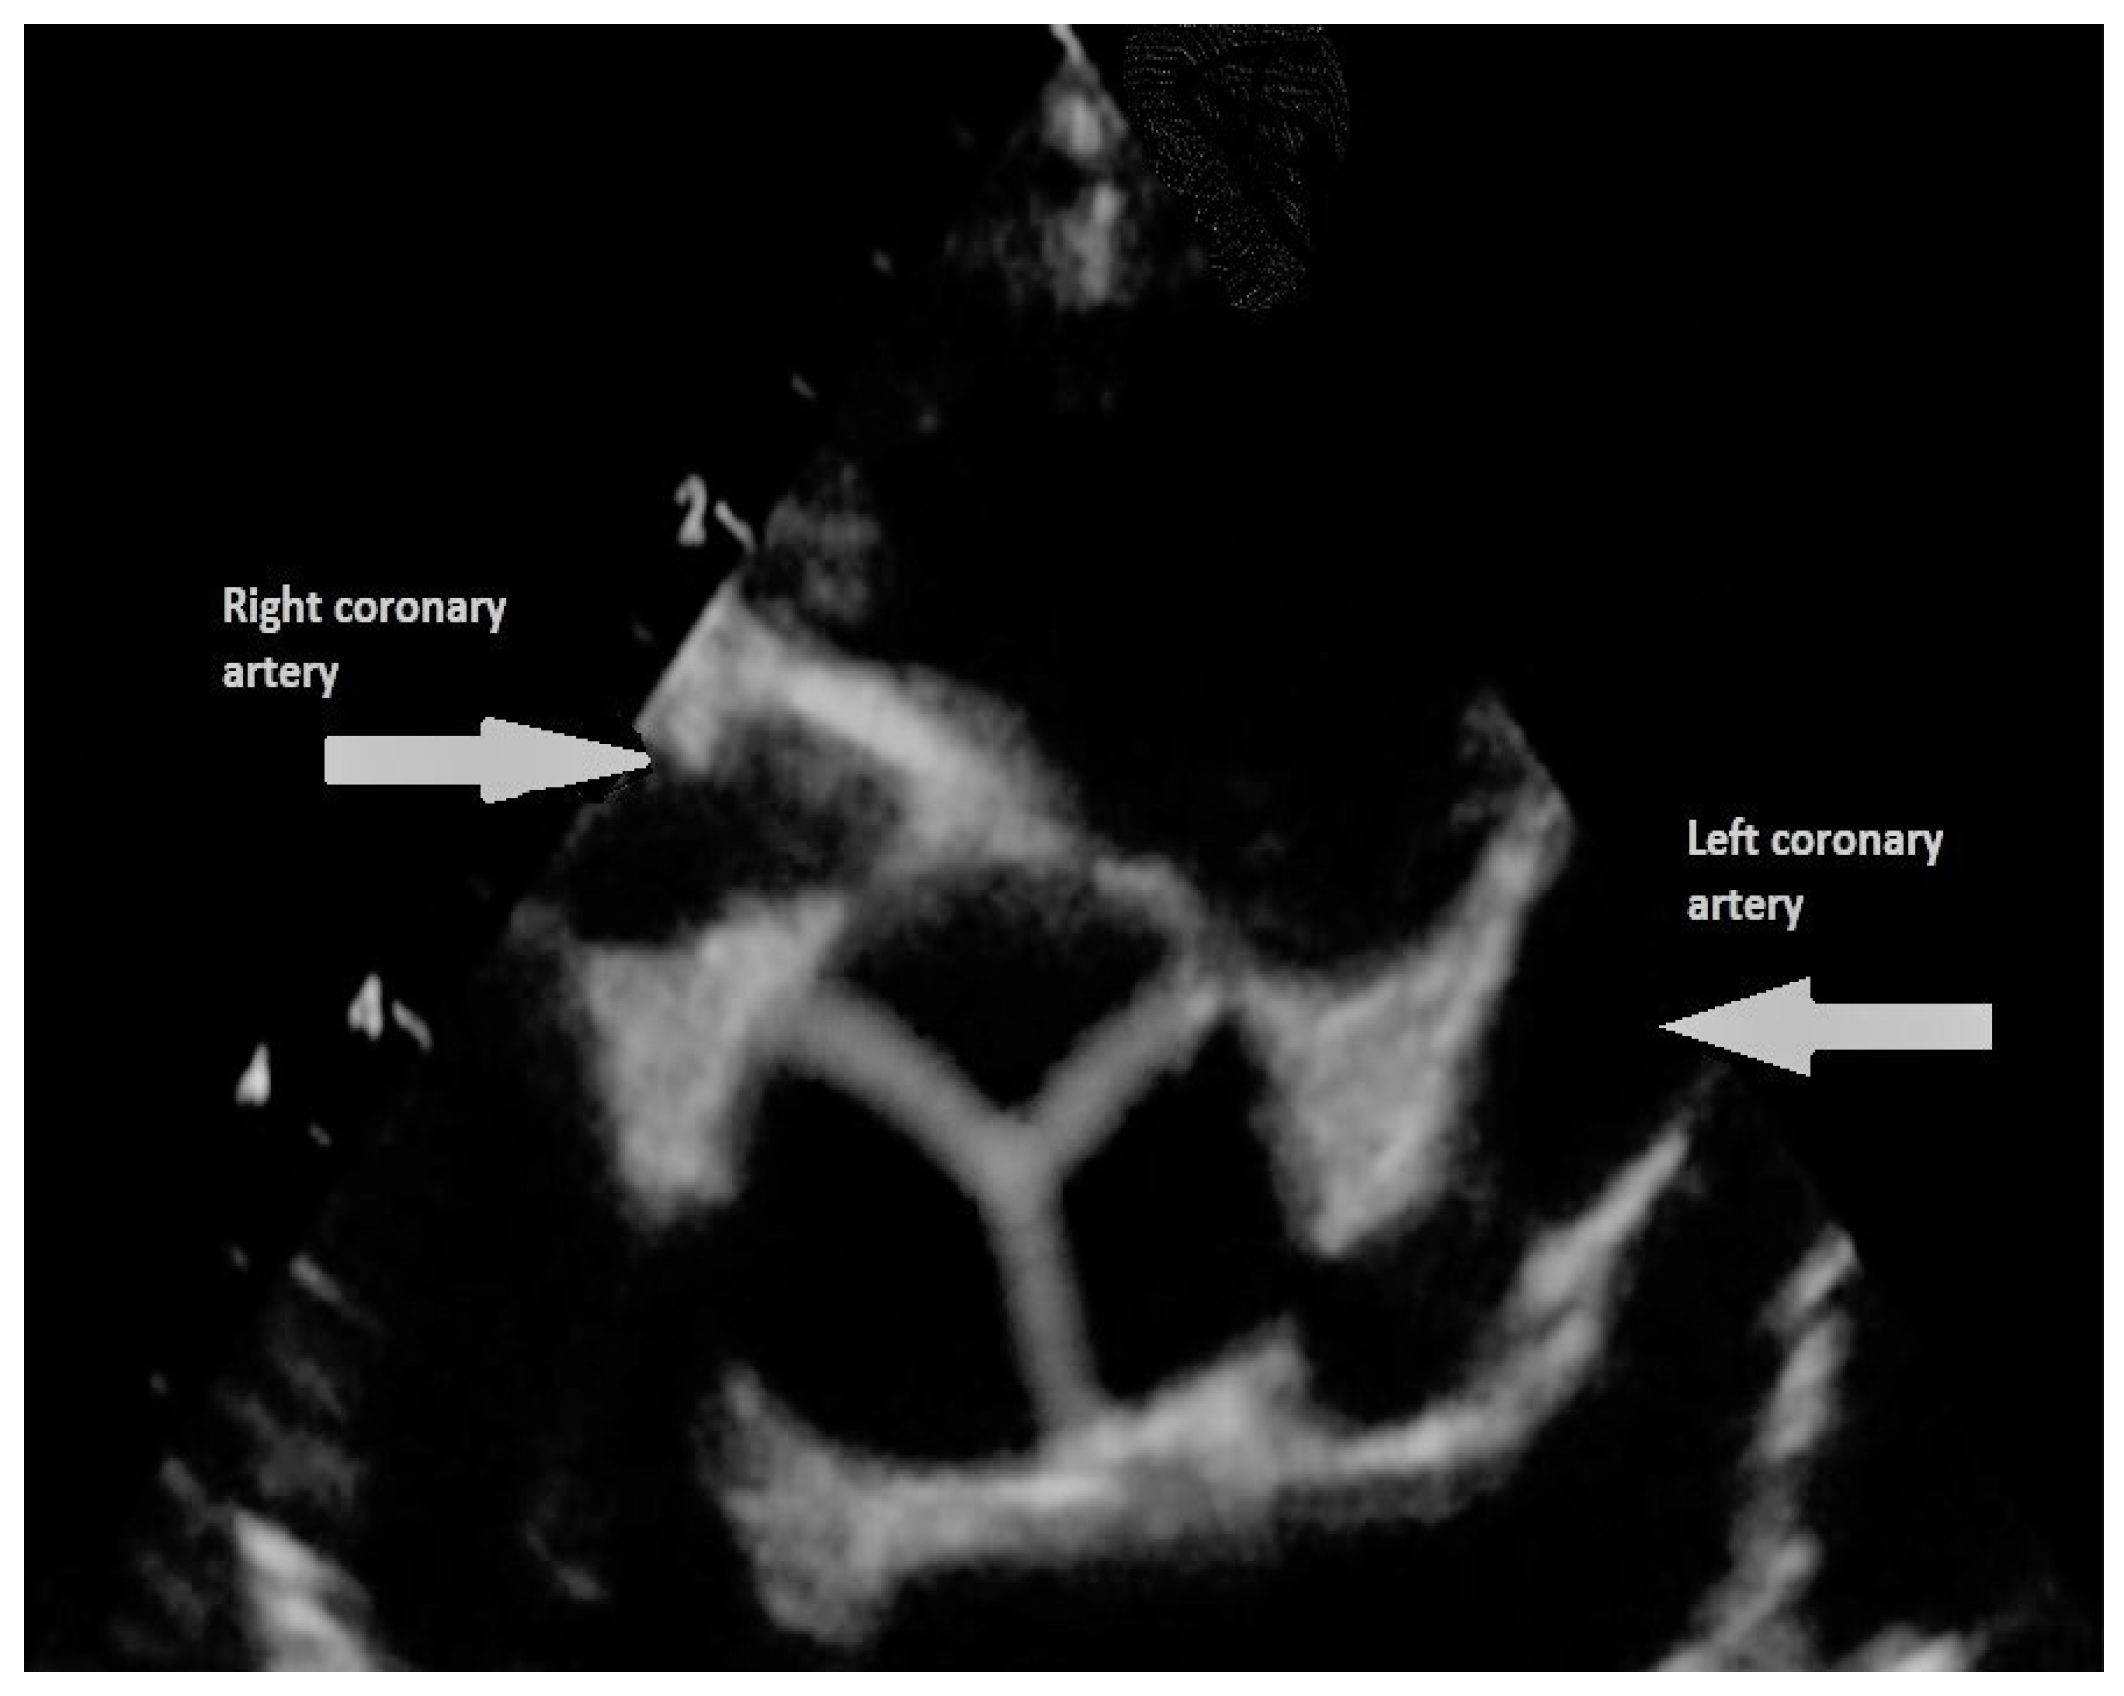

- Bonhoeffer, P.; Bonnet, D.; Piéchaud, J.F.; Stümper, O.; Aggoun, Y.; Villain, E.; Kachaner, J.; Sidi, D. Coronary artery obstruction after the arterial switch operation for transposition of the great arteries in newborns. J. Am. Coll. Cardiol. 1997, 29, 202–206. [Google Scholar] [CrossRef]

- Ou, P.; Celermajer, D.S.; Marini, D.; Agnoletti, G.; Vouhé, P.; Brunelle, F.; Le Quan Sang, K.H.; Thalabard, J.C.; Sidi, D.; Bonnet, D. Safety and accuracy of 64-slice computed tomography coronary angiography in children after the arterial switch operation for transposition of the great arteries. JACC Cardiovasc. Imaging 2008, 1, 331–339. [Google Scholar] [CrossRef]

- Ou, P.; Khraiche, D.; Celermajer, D.S.; Agnoletti, G.; Le Quan Sang, K.H.; Thalabard, J.C.; Quintin, M.; Raisky, O.; Vouhe, P.; Sidi, D.; et al. Mechanisms of coronary complications after the arterial switch for transposition of the great arteries. J. Thorac. Cardiovasc. Surg. 2013, 145, 1263–1269. [Google Scholar] [CrossRef]